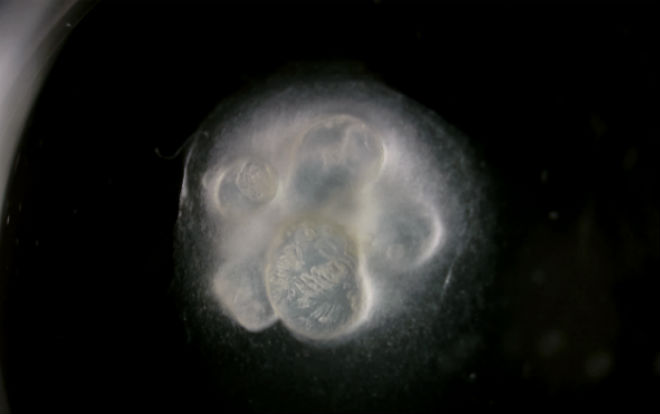

▲体外培养的“迷你”胃(图片来源:sciencemag)过去10年来体外细胞培养技术取得了快速的发展,现在,细胞培养已经不只是传统的平面培养模式,通过各种方式可以使细胞在体外也能形成三维结构。通过3D细胞培养技术,科学家们现在已经能够在实验室里制造出多种微缩版的人体器官,这包括肝、胰、胃、心、肾等等,这些“迷你”器官在体外模拟疾病过程以及测试药物方面有着广泛的用途。近日,《Development》杂志以专刊的形式回顾了这一领域的最新发展。这些在实验室中制造出来的“迷你”器官尽管非常小,但是在结构上可以模仿出许多脏器内部的精细结构,比如说肾脏内部的肾小管、大脑皮层的褶皱、以及小肠内部的粘膜和绒毛。不过,它们和真正的人体器官还有许多的不同之处,其中最重要的不同在于这些体外“迷你”器官缺乏血管,而血液对于人体器官的生长发育和正常功能都是必不可少的。因此,这些“迷你”器官只能永远处于“迷你”的状态,目前还无法培育出任何接近实际大小的体外器官。严谨的科学家们把这些体外培养的“迷你”器官称之为“类器官”,它们可以模拟器官形成的最早期的过程,同时可以用于研究诸如基因突变等因素如何影响正常器官的功能。